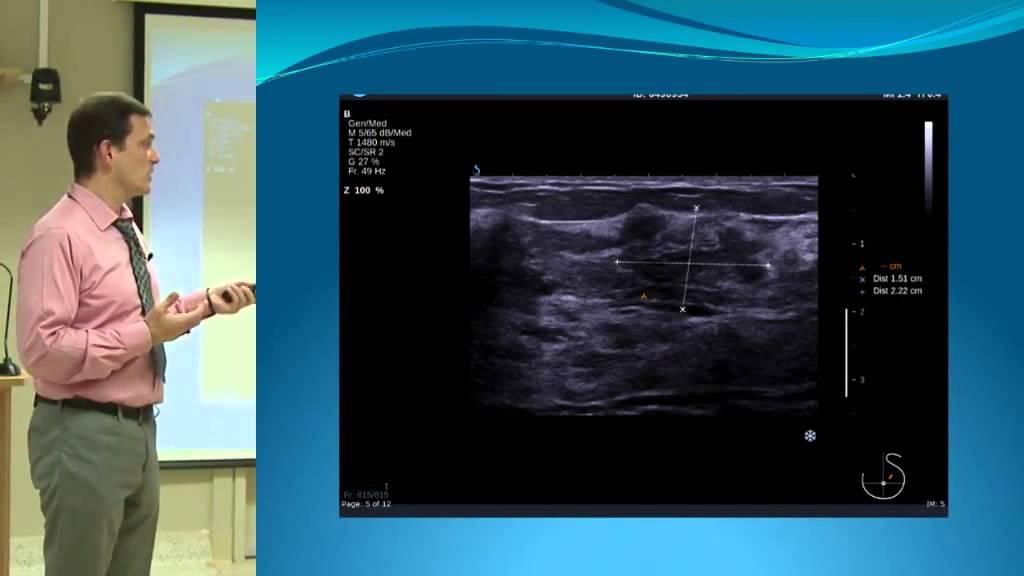

Exploration d'un nodule classé TIRADS 5 en échographie.

Explication des critères de son classement et comparaison avant après à 3 ans d'évolution chez cette patiente en altération de l'état général.

La classification TIRADS est détaillée à la fin de cette vidéo afin de vous aider à coter vos nodules.